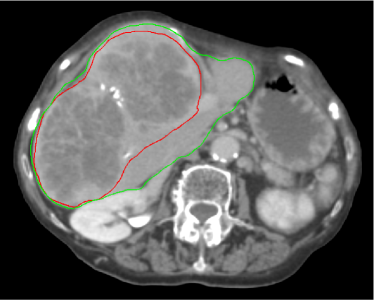

The patient who motivated this work presented with a very large liver tumor (a metastatic lesion originating from chemo-refractory colorectal cancer). The initial target volume in the first treatment stage was assessed using 4D CT, resulting in an internal gross target volume (IGTV) of 1218 cc in size (which incorporated a peak-to-peak motion of 4.15 mm as defined at the fiducials). In comparison, the total volume of normal appearing liver was 870 cc. Thus, the tumor mass accounted for 58% of the total liver volume. The patient was treated in two stages separated temporally by a period of four months. Figure 1 shows the radiotherapy planning CT for the first stage (a) and the second stage (b). Until the most recent follow-up visit (6 months after the second stage), the liver lesion remains stable.

Figure 1: Planning CT image of the patient for the first treatment stage (a) and the second stage (b) four months later. The corresponding CT slices for the two time points are chosen based on the bony anatomy of the spine. The red contour shows the GTV, the green contour corresponds to the liver.

Both treatment stages used a dose painting strategy in which the planning target volume was subdivided into two parts: a low dose PTV was constructed via a 3 mm isotropic expansion of the IGTV; a high dose PTV was constructed by a 1 cm contraction of the low dose PTV. This allowed for a dose reduction to normal radiosensitive tissue adjacent to the target volume while delivering a high SBRT dose to the interior target volume. In the first stage the low dose PTV was treated to 18 Gy in 3 fractions while the high dose PTV was treated to a total of 36 Gy in 3 fractions concurrently. After the four month intermission, the patient returned to be rescanned and treated using the new imaging information. The physician-defined IGTV was 499 cc (37% of total liver volume), and thereby substantially smaller than in the first stage (see figure 1b). The prescribed dose to the low dose PTV for stage two was 20 Gy in 3 fractions, while the high dose PTV received 30 Gy in 3 fractions. Deformable registration was performed in order to assess the cumulative dose to secondary organs at risk, such as the spinal cord and the kidneys. Through the dose painting approach, the mean dose to the non-involved liver (i.e. total liver without GTV) was reduced to 10.8 Gy in the first stage, and 13.3 Gy in the second stage.